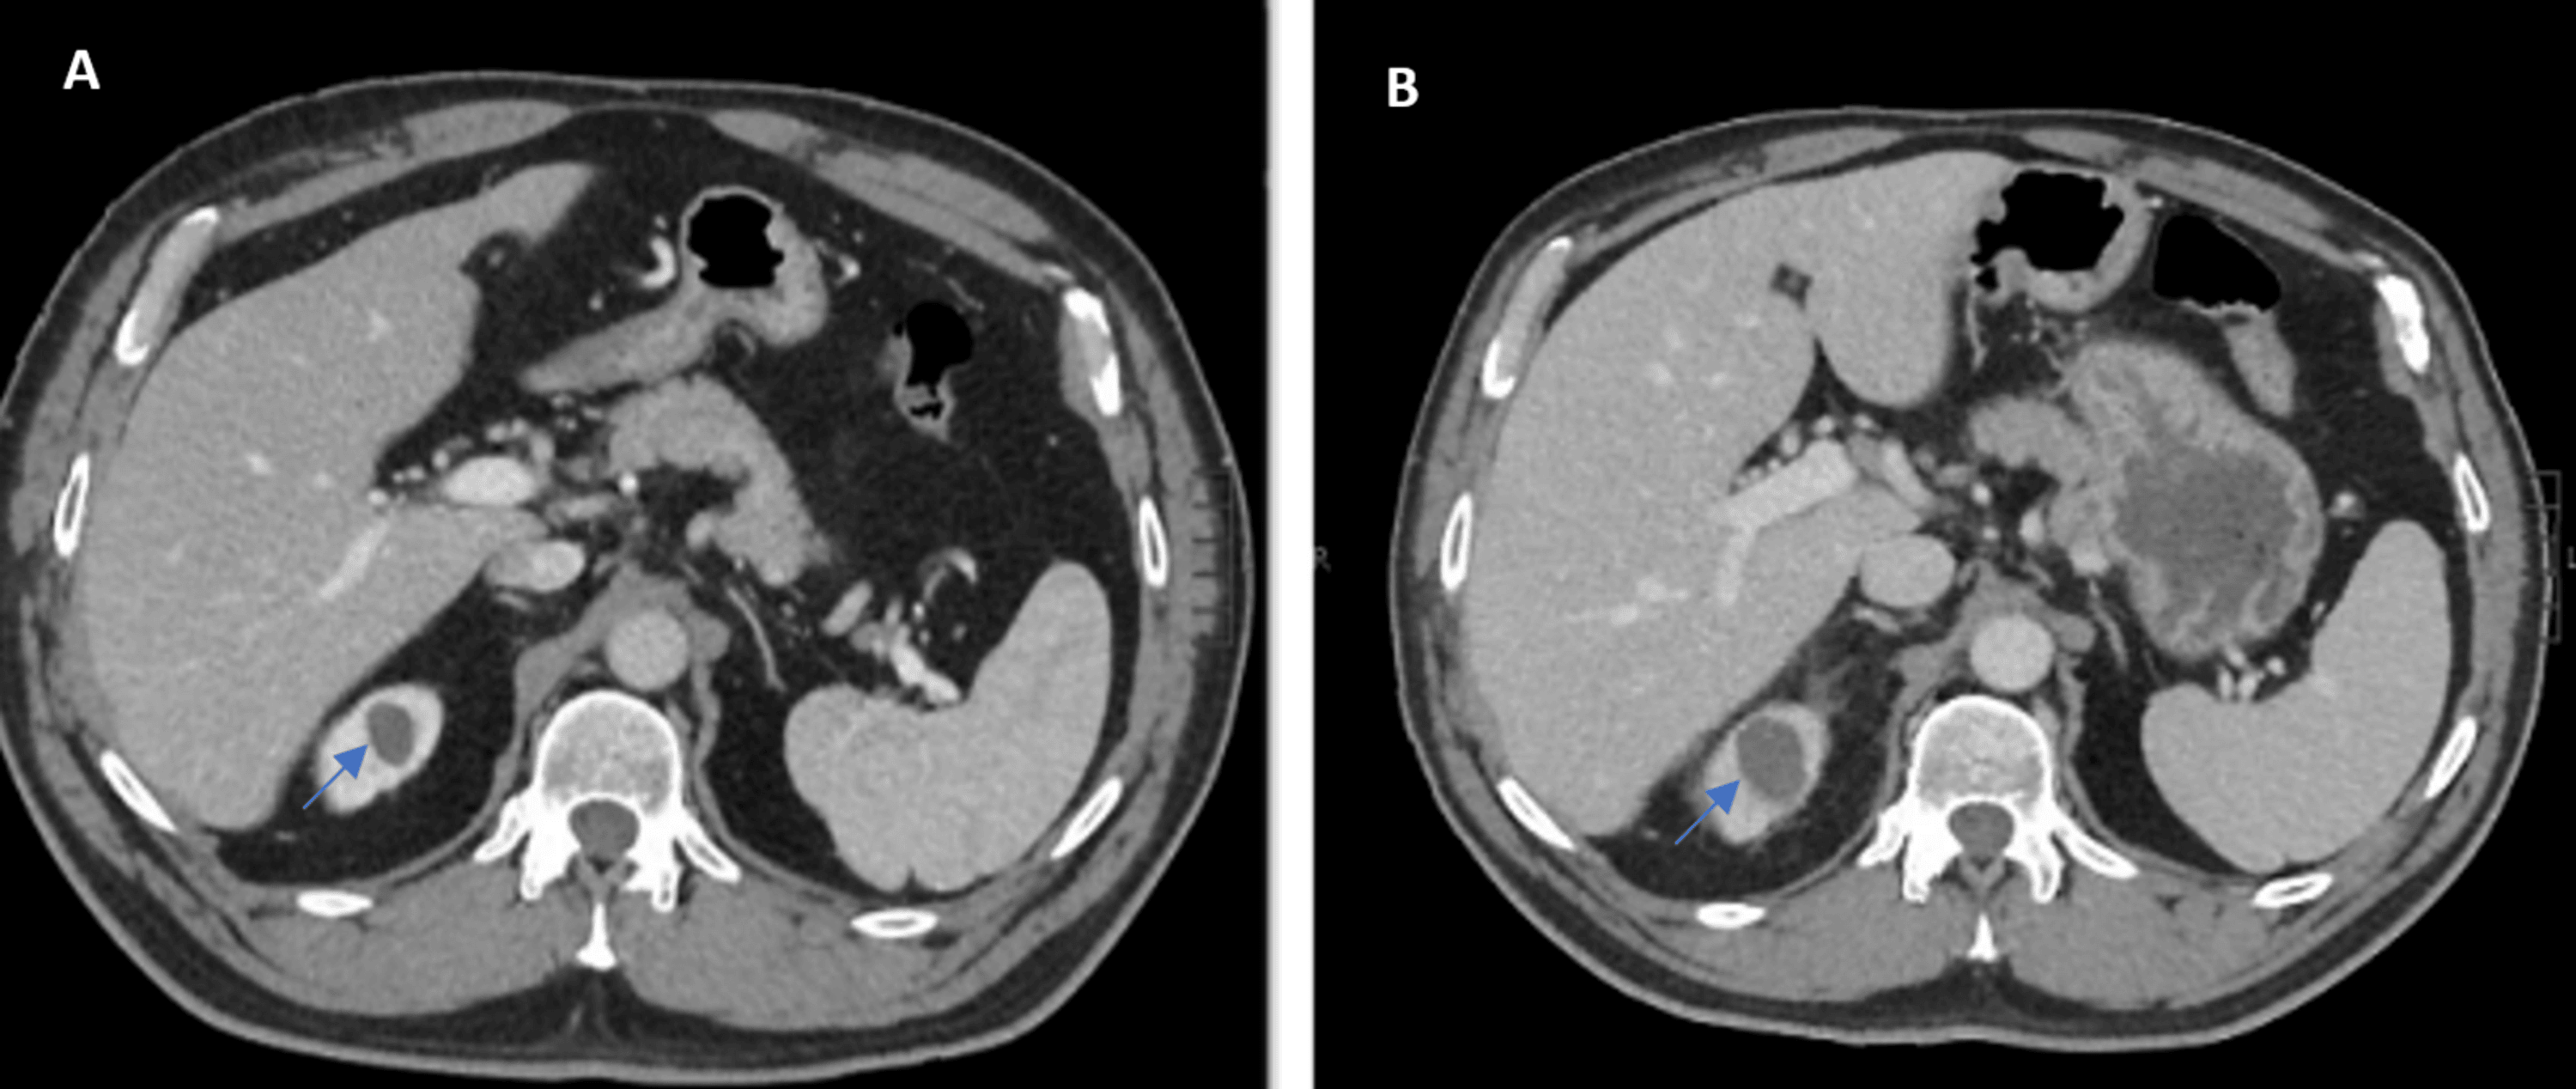

Benign hyperdense renal cyst. Axial CTscan before (a) and after Water Density Renal Cyst Renal cysts are sacs of fluid that form in the kidneys. But more often, kidney cysts are a type. There are two types of kidney cysts: Kidney cysts can occur with disorders that may impair kidney function. As you get older, cysts can form on the. One or more simple cysts may form within the. Kidney cysts are round pouches. Water Density Renal Cyst.

Benign hyperdense renal cyst. Axial CTscan before (a) and after Water Density Renal Cyst Renal cysts are sacs of fluid that form in the kidneys. Kidney cysts are round pouches of fluid that form on or in the kidneys. Simple cysts are individual cysts that form on. Kidney cysts can occur with disorders that may impair kidney function. Kidney cysts (renal cysts) are usually small, round sacs that have a thin wall and contain. Water Density Renal Cyst.